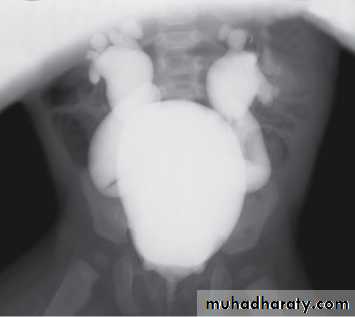

Grading of VUR

The degree of reflux is graded I–V.

Grading is based on the appearance of contrast agent in the collecting system during voiding cystourethrography (VCUG(.

MCUG